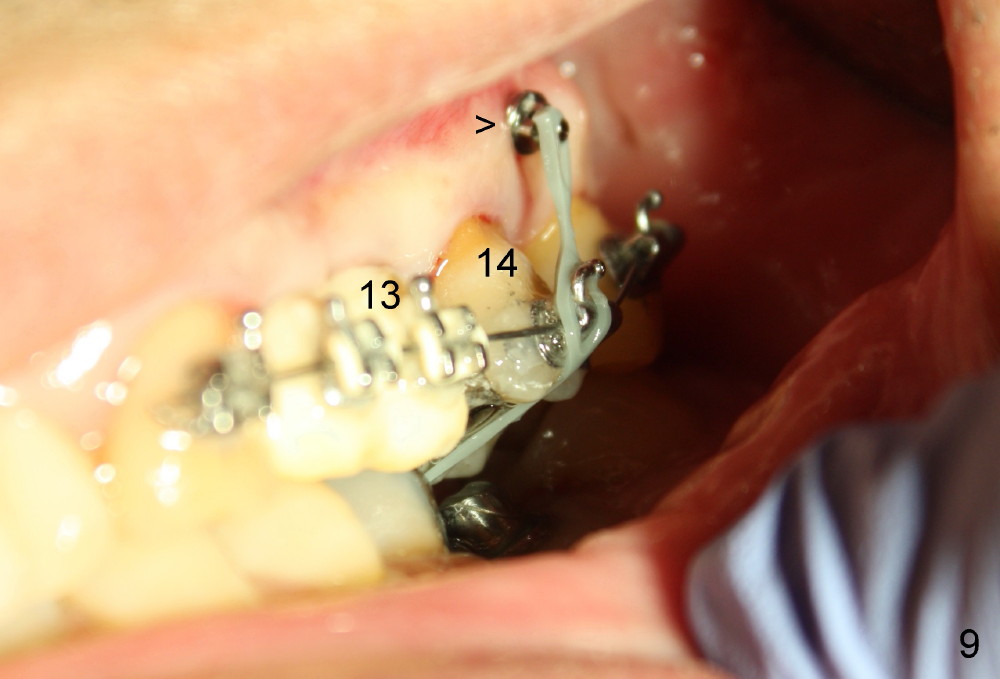

A 51-year-old man needs implants at the sites of #12,13,19 (Fig.1). The teeth #12 and 13 are extracted. An implant is placed at #19 (Fig.2 <). After osteointegration, an abutment is placed (Fig.2 A). The opposing tooth, #14, is found supraerupted. Two mini-implants are placed at the mesiobuccal and distolingual areas of #14 (Fig.3 (mirror view) <) and a power chain (*) is placed for intrusion. In the next 8 months, these 2 mini-implants become loose. Two new mini-implants are placed in the mesiolingual and distobuccal regions (Fig.4 ^). The one in the distobuccal region is loose after a while (Fig.6,7 >). In brief, mini-implants are not efficient in intrusion. At this time, the implants at the sites of #12,13 apparently osteointegrate (3 months post placement) and abutments are placed (Fig.4). Provisional crowns are fabricated (Fig.5). Brackets are placed between #11 and 15 with the bracket at #14 placed more coronally than those of the neighboring teeth (Fig.6-8). Mesially there are two excellent anchorages (#12,13) as well as the mesiolingual mini-implant. The distal anchorage is #15. In the next 5.5 months, the tooth #14 is intruded (Fig.9,10), but the 2nd molar is mobile (not as strong as #14). A longer mini-implant is placed in the distobuccal corner (>, more apical than before (Fig.7)). The distobuccal mini-implant is found to be mobile in 3 weeks (Fig.11). It appears that there is enough clearance for restoration of #19 (Fig.12). Power chains are placed between the mesiolingual mini-implant and #14 buccal tube until the appointment for crown prep. In this way, the lingual cusps may ascend (Fig.13 red arrow), while the buccal ones may descend (black arrow). The occlusal clearance will be more favorable.